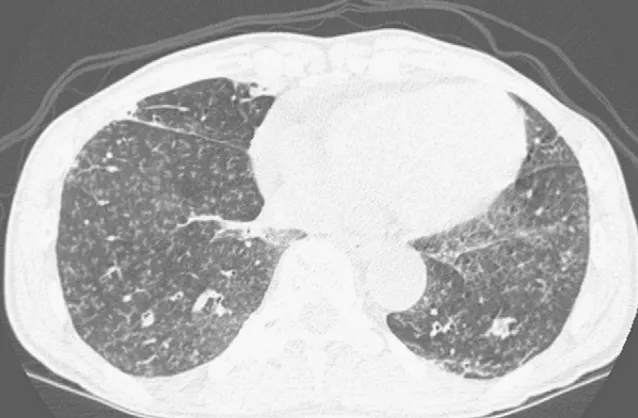

胸部CT示两下肺弥漫分布细胞粟粒样小结节影。

DAB的胸片表现包括弥漫性小结节影和非特异性间质浸润,实变相对少见,这是吸入性肺炎的常见表现。高分辨率CT扫描显示弥漫性小叶中心性结节,呈现树芽征,这与其他弥漫性细支气管疾病相似,如弥漫性泛细支气管炎(DPB)、支原体肺炎,人类嗜T淋巴病毒1型感染,变态反应性支气管肺曲霉菌病,分枝杆菌感染,滤泡性细支气管炎,囊性纤维化。

特别是,DAB应该与DPB区分,因为它们有太多临床和影像学表现相似之处。DPB是一种发生在细支气管和邻近小叶中央区域的特发性慢性炎症性疾病,主要发生亚洲人。DPB常伴有鼻窦炎,而DAB不是。

当然,由于DAB和DPB临床和影像学很类似,有时难以区分,必要时就需要外科肺活检。